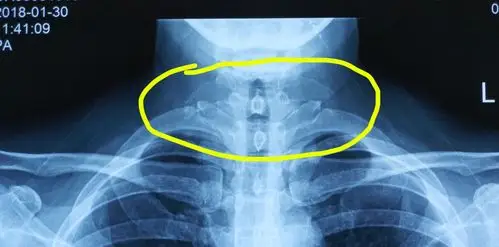

颈椎第一横突病变引起头面部疼痛